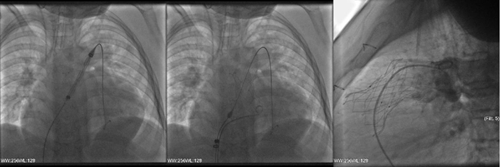

術(shù)中,手術(shù)團(tuán)隊(duì)僅在患者大腿根部做一個(gè)小切口,穿刺股動(dòng)脈和股靜脈,便順利將肺動(dòng)脈瓣膜植入目標(biāo)位置。手術(shù)全程不到1個(gè)小時(shí),且無需體外循環(huán)和氣管插管,無需輸血,傷口無需縫針。術(shù)后檢查顯示瓣膜植入位置良好,肺動(dòng)脈瓣膜無反流、無瓣周漏、無壓差,效果理想。目前,患者已順利出院。

肺動(dòng)脈瓣植入過程